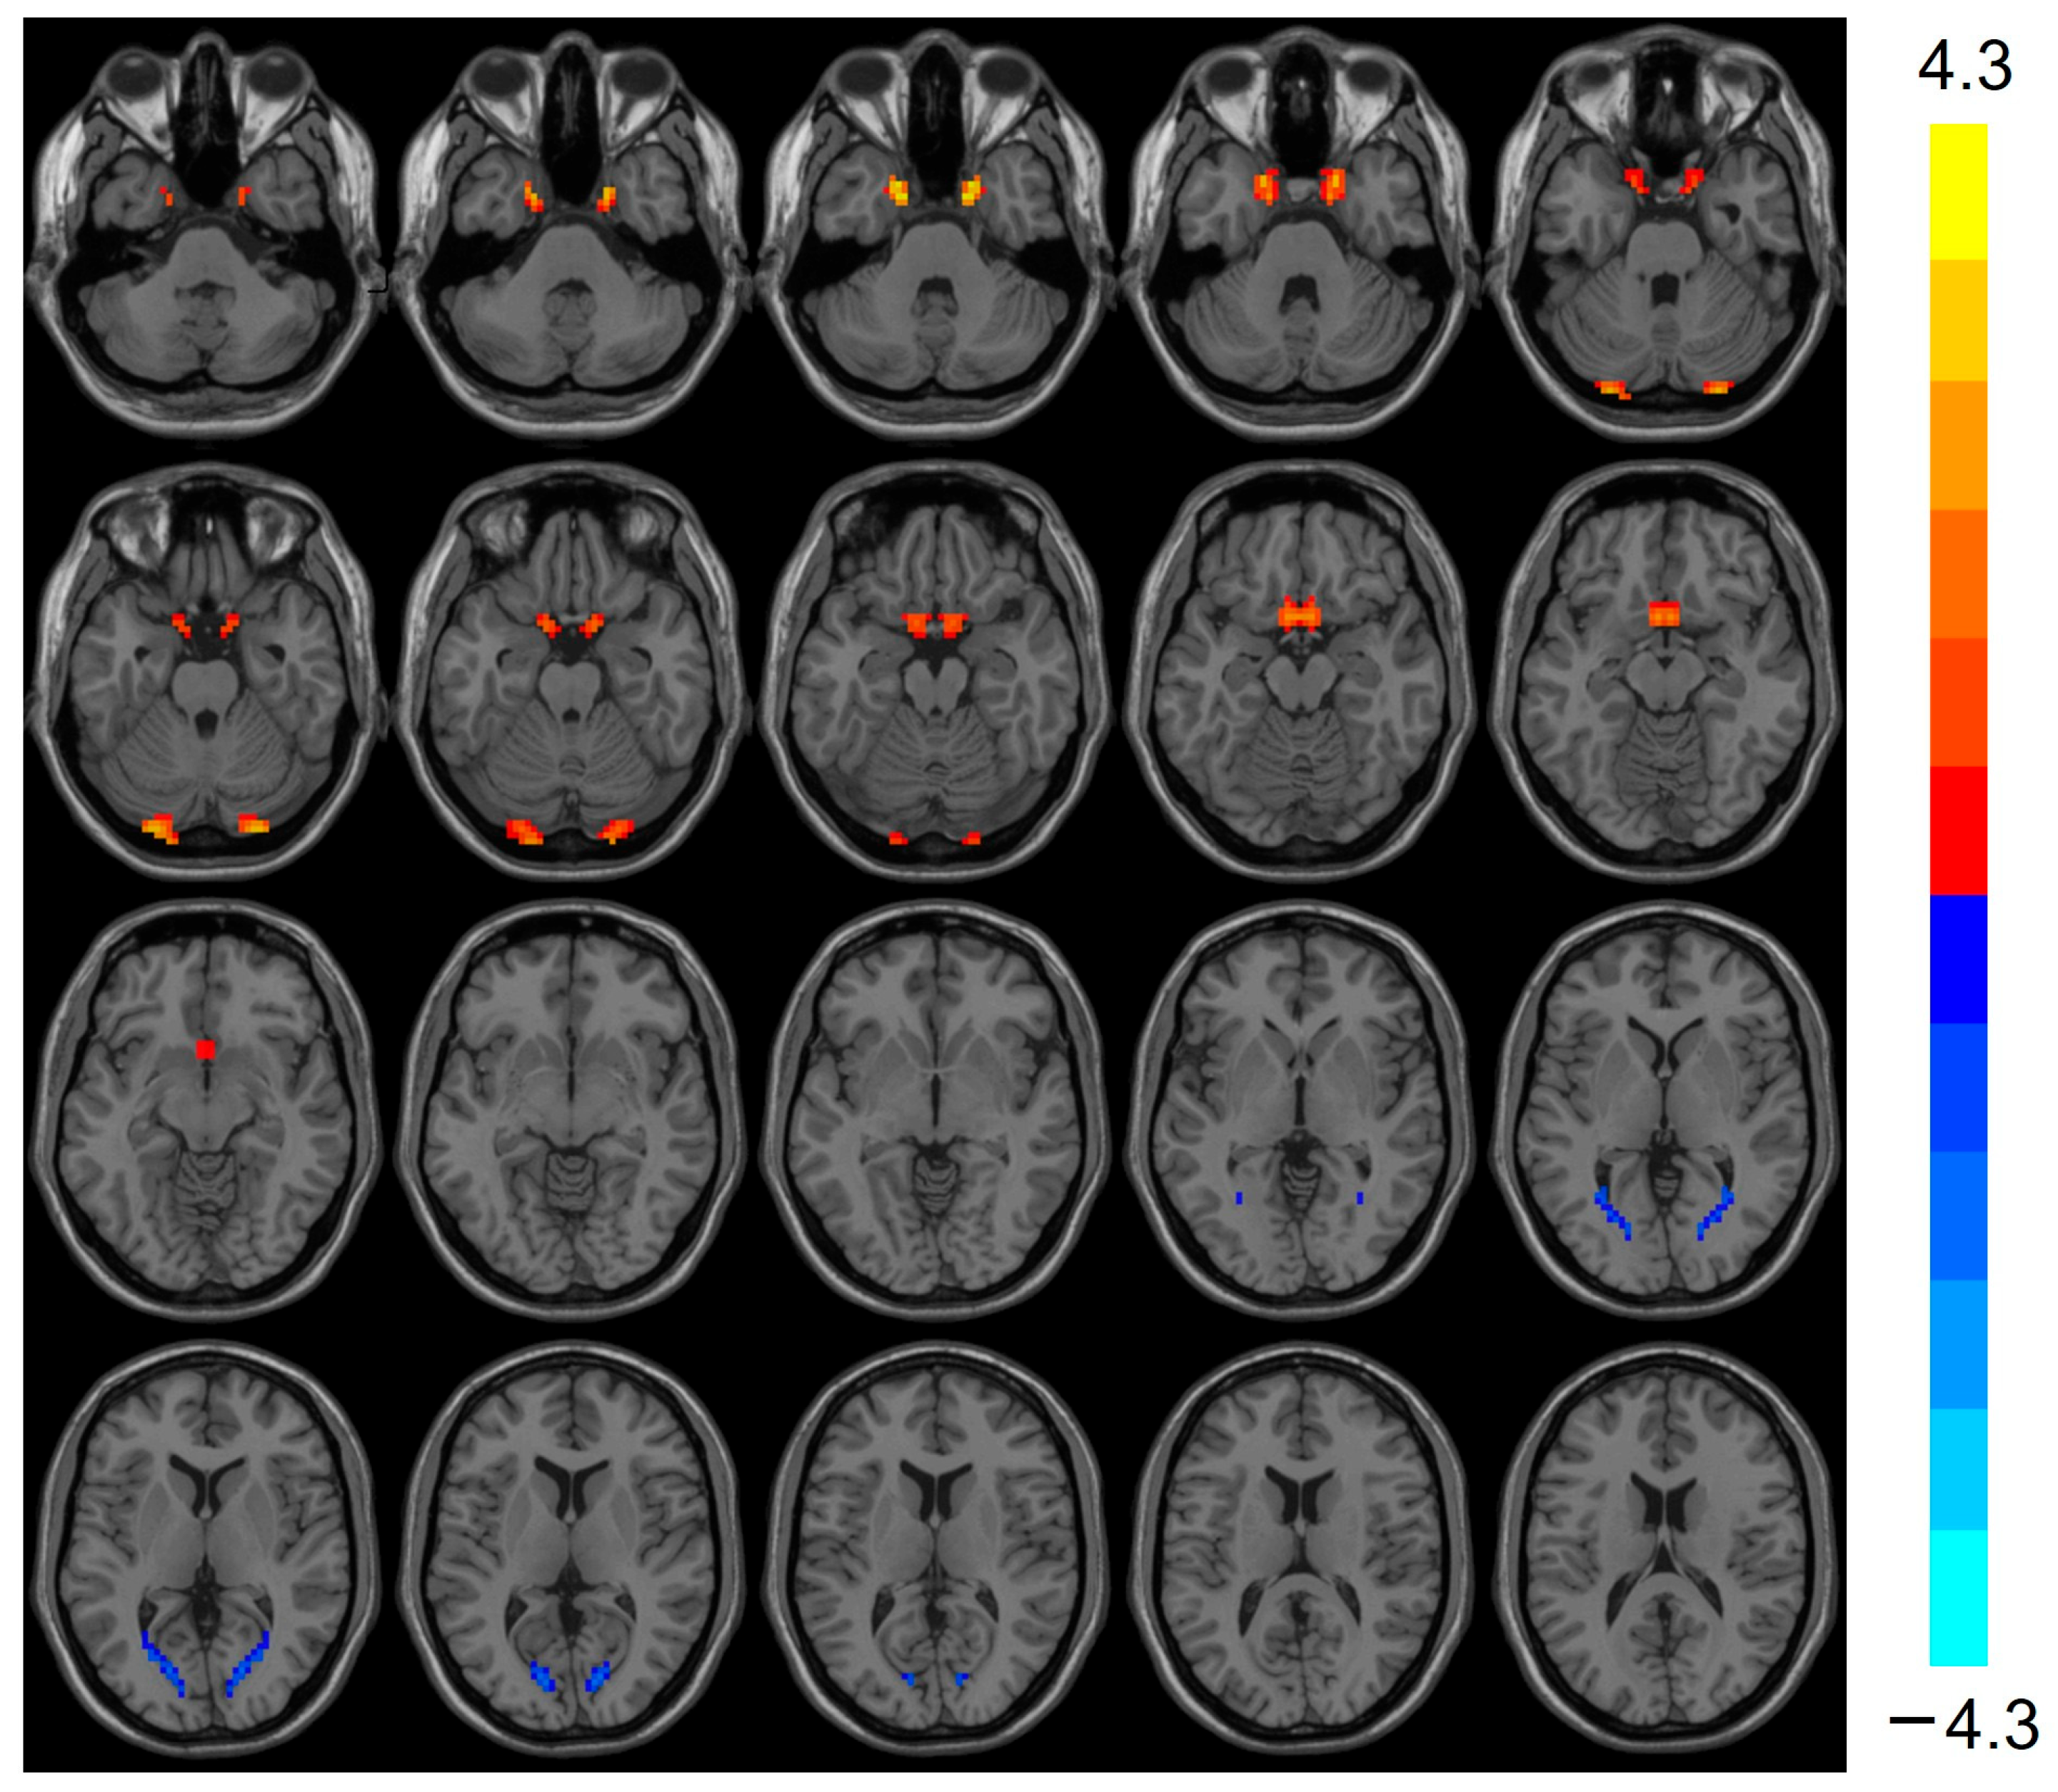

3.3. VMHC Analysis Results

| Regions | Clusters Voxels | Peak MNI Coordinate | T-Values | ||

|---|---|---|---|---|---|

| x | y | z | |||

| Cerebelum_Crus1_L | 22 | −27 | −93 | −24 | 3.803 |

| Cerebelum_Crus1_R | 22 | 27 | −93 | −24 | 3.803 |

| Calcarine_L | 49 | −15 | −78 | 9 | −3.424 |

| Calcarine_R | 49 | 15 | −78 | 9 | −3.424 |